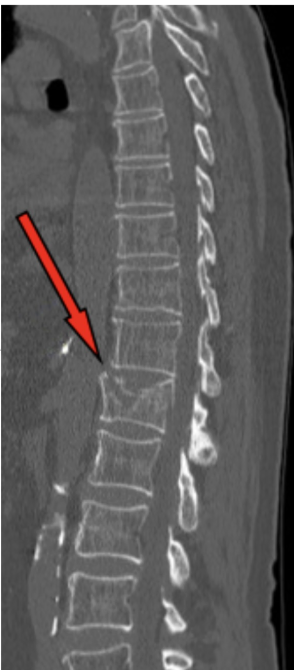

Wat is een compressiefractuur/geinclaveerde fractuur?

Inzakking van bot (vaak wervels, osteoporose)

compressiefractuur

kenmerkend is het inzakken van trabeculair bot, vaak in wervel lichamen (osteoporose)